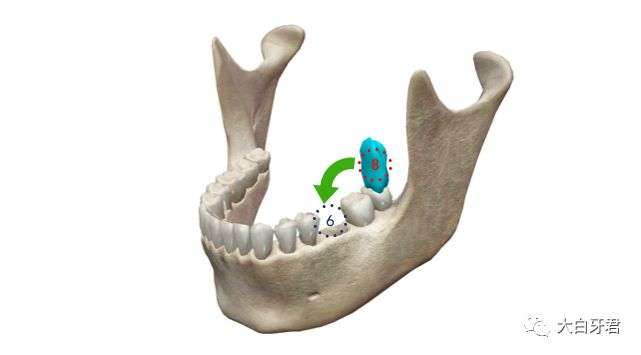

最后,还可以使用自体牙齿再植技术,在缺失的牙齿拔除后的即刻,把其他位置的智齿(往往是恰好需要拔掉的智齿)完整拔除、 迅速移植到缺牙处,这个牙齿会在未来的一段时间内逐渐牢固,发挥余热。

同样的6号牙缺失,条件合适的话,可以使用上面的8号牙(智齿)拔除后即刻再植到缺失的位置,无需镶牙。

当然,这种方案同样有局限性,不是所有的情况都可以适用。